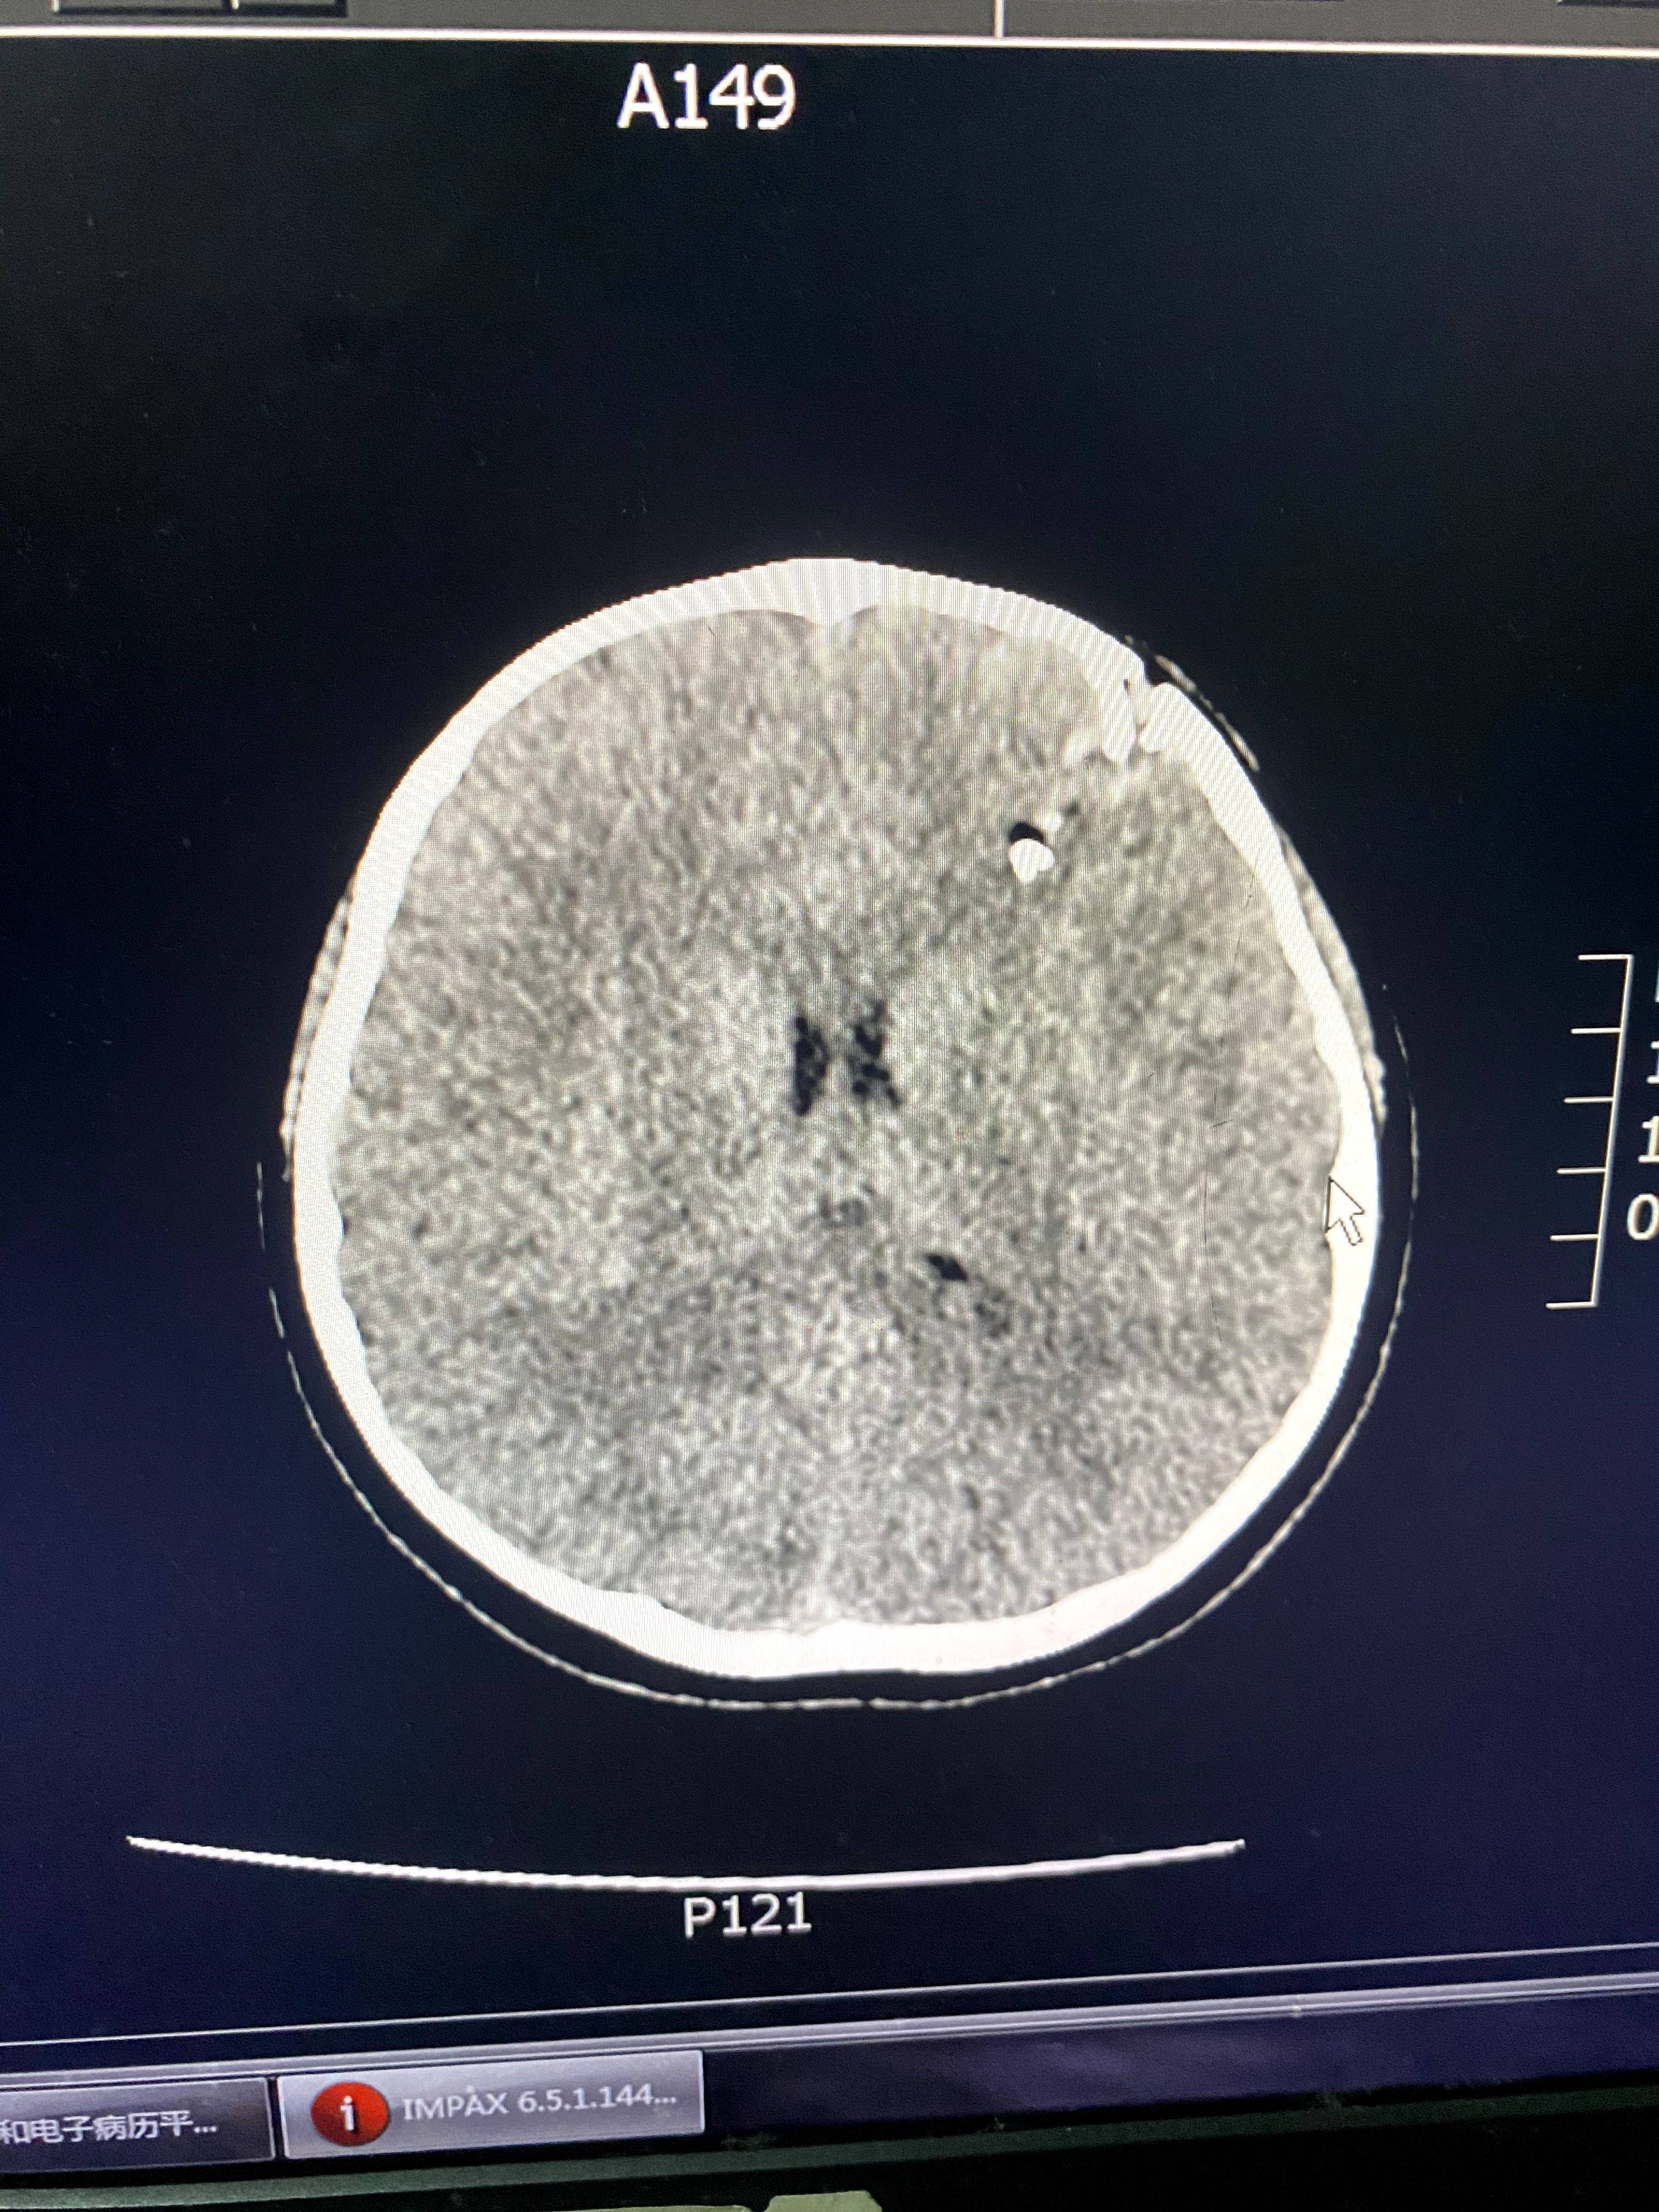

班主任就站在孩子身边。郭洋还没来得及多问,医生就从CT室匆匆赶来,指着电脑上的片子告诉郭洋,“颅骨已经碎了,颅内疑似有异物,要马上做开颅手术。”郭洋说,女儿从小到大几乎没受过什么伤,连感冒都少。听到“开颅”两个字时,她“腿都吓软了”。

后来的伤情鉴定结果显示,星星的头面部软组织裂伤,开放性颅骨骨折伴硬脑膜破裂,颅内出血,颅内异物,脑挫裂伤,伤情构成重伤二级。这起事件当年引起了媒体的广泛关注,涉事老师被判处有期徒刑五年,并被禁止从事密切接触未成年人的工作。

CT显示,星星的颅骨碎裂,颅内有异物。讲述者供图